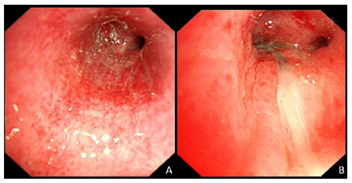

患者,女性,67岁,因"咳嗽伴发热20余天,咯血2 d"入院。患者于2022年8月28日无明显诱因出现咳嗽、咳白黏痰,量不详。伴发热,体温最高37.7℃,发热呈阵发性,无畏寒、寒战,无咯血、胸痛、盗汗,无胸闷、憋气,曾自行服用"头孢"治疗,症状未见明显好转。2022年9月5日上述症状加重,伴胸闷、憋气,就诊于当地社区医院,给予肌注药物治疗(具体不详),症状未见明显好转,就诊于当地上级医院,胸部CT示双肺感染性病变,双上肺及右肺中叶为著(未见CT影像)。血常规示:白细胞15.3×109/L,中性粒细胞13.84×109/L,淋巴细胞计数0.87×109/L ,单核细胞1.2×109/L,CRP 181.27 mg/L;细菌培养:耐药铜绿假单胞菌;G试验、GM试验均为阴性。给予左氧氟沙星、比阿培南、替加环素、甲泼尼龙、喘定治疗,症状稍缓解。9月17日上述症状加重,咯血,为暗红色,量不详,伴有发热,体温最高38.2℃,于9月19日就诊于我院。患者既往高血压病史10余年,最高血压达200/90 mmHg。有糖尿病病史半个月余,未应用降糖药,血糖、血压均控制不佳。入院查体:体温36.1℃,脉搏82次/分,呼吸19次/分,血压115/69 mmHg,神志清,精神可,口唇无紫绀,听诊双肺呼吸音粗,可闻及干湿啰音。辅助检查:2022年9月19日胸部CT:双肺多发斑片、片状高密度影及结节灶,气管内斑片影(图1A);PCT 1.02;血常规+CRP:白细胞计数15.37×109/L,中性粒细胞计数13.61×109/L,C反应蛋白233.14 mg/L;尿常规:酮体1+,尿葡萄糖3+。初步诊断为:1.重症肺炎;2.肺真菌感染;3.侵袭性肺曲霉菌病(?);4.高血压病3级(极高危);5.2型糖尿病糖尿病酮症。

2022年9月20日,血常规+CRP:白细胞计数9.08×109/L,中性粒细胞8.01×109/L,血红蛋白98 g/L,C反应蛋白286.31 mg/L;呼吸道13种病原体检测:铜绿假单胞菌阳性;G试验和GM试验均为阴性。2022年9月22日,支气管镜检查:右肺上叶前段支气管新生物阻塞,双肺支气管炎性改变(图2A)。BALF给予活检并送mNGS检查:铜绿假单胞菌、代尔根霉、烟曲霉、EB病毒、人疱疹病毒1。病理结果:黏膜重度慢性炎,BALF未见肿瘤细胞。肺泡灌洗液真菌培养:烟曲霉;肺泡灌洗液细菌培养:耐药铜绿假单胞菌。复查CT示双肺多发空洞,考虑脓胸并空洞形成,较2022年9月19日CT片加重(图1B),给予哌拉西林钠他唑巴坦钠4.5 g 2次/d静滴联合伏立康唑0.2 g 2次/d静滴治疗3 d后患者仍有低热,伴咳嗽、咳痰、咯血,炎症指标改善不明显,调整抗生素为:伏立康唑0.2 g 2次/d静滴(2022年9月24日-2022年10月9日)、美罗培南1 g tid静滴(2022年9月27日-2022年10月14日)、硫酸阿米卡星0.8 g 1次/d静滴(2022年9月29日-2022年10月3日)。复查CT示双肺多发空洞,较2022年9月24日CT片右肺病变范围增多(图1C)。遂予以结合药敏给予加用两性霉素B胆固醇硫酸酯体2 mg(50~200 mg)泵入及两性霉素B 5mg 2次/日雾化(2022年9月29日-2022年10月10日)抗感染治疗辅以地塞米松3 mg 1次/d静脉注射激素抗炎。考虑患者感染重,治疗难度大,院内组织多学科讨论后,先后行气管镜下两性霉素B局部注射治疗3次。患者症状和氧合逐渐改善,复查CT示双肺多发实性密度并空洞,局部伴气液平,空洞较前缩小,双肺部分斑片影新增(图1D)。10月11日CT示双肺多发实变并空洞,局部伴气液平,较2022年10月4日CT吸收好转较(图1E)。复查气管镜示右中叶管口较前改善(图2B)。治疗期间多次复查曲霉感染相关指标:曲霉菌IgG抗体均<31.25 AU/ml;曲霉半乳甘露聚糖测定均<0.499。

侵袭性肺曲霉病临床表现和影像学表现多样且无特异性,多由曲霉菌侵袭肺泡和细支气管壁出现支气管周围实变影、支气管扩张征、小叶中心型微小结节影、树芽征和磨玻璃样等改变逐渐演变为曲霉菌侵袭血管出现致密、边界清楚的病变(伴或不伴晕征)、空气新月征、空洞、楔形/节段性或大叶性病灶为特征性的影像学表现[5]。上述典型的影像学特征在该例患者中可见,其病理基础是曲霉侵犯肺血管,形成出血性肺梗塞。当肺小血管梗死后局部形成肺结节或实变病灶。常位于肺外周近胸膜处,肺部呈单发或多发病灶,病灶周围出血,在影像学上出现晕轮征。约10~15 d后肺结节病灶或肺实变区开始液化、坏死,影像学上出现空腔阴影或新月征。